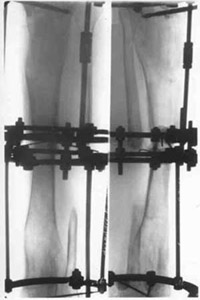

| Joining fragments of spin-bone with electrostimulation and osteoreparation. |

Results of treatment. | |